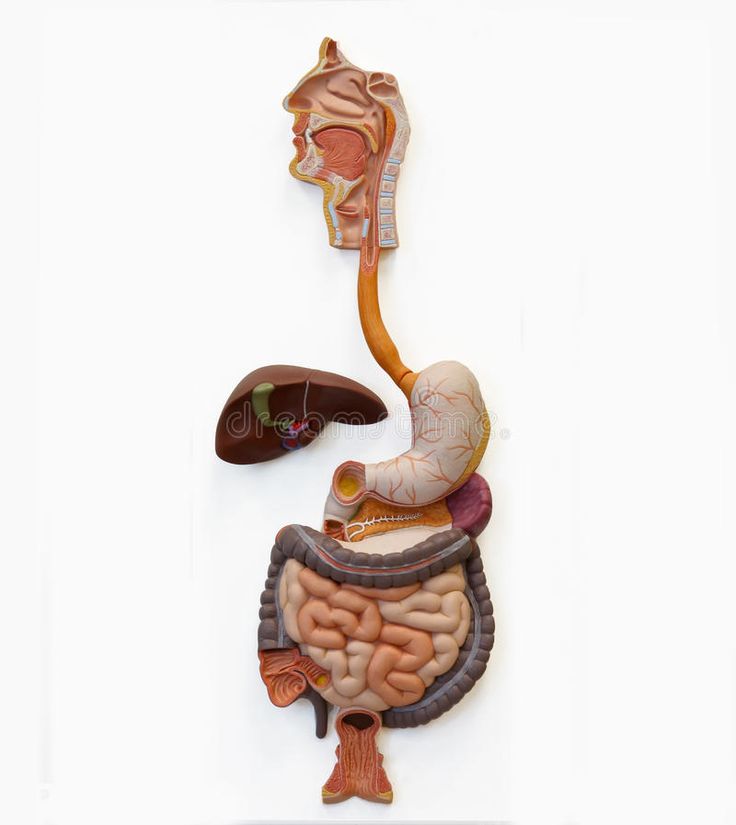

Курс "Пищеварительная система" содержит учебно-методические материалы по анатомии, гистологии, физиологии пищеварительного тракта, освещает вопросы метаболизма, биохимии пищеварительных ферментов, рационального питания, сбора анамнеза у пациентов с нарушением пищеварения.

Неделя 1. ВВЕДЕНИЕ В ПИЩЕВАРИТЕЛЬНУЮ СИСТЕМУ. ПОЛОСТЬ РТА.

ГЛОТКА.ПИЩЕВОД. ЖЕЛУДОК. ТОНКАЯ И ТОЛСТАЯ КИШКА

Общий план строения пищеварительной трубки. Особенности слизистой оболочки, ее эпителия в пищеводе и разных отделах желудка. Железы пищевода. Железы желудка разных отделов. Место переходов: из пищевода в желудок и из желудка в кишку.

- Особенности строения слизистой оболочки тонкой кишки: ворсинки, крипты, эпителий, его клеточный состав. Различия в строении двенадцатиперстной, тощей, подвздошной кишки. Морфологическая характеристика толстой кишки, клеточный состав эпителия крипт. Лимфоидная ткань тонкой и толстой кишки.